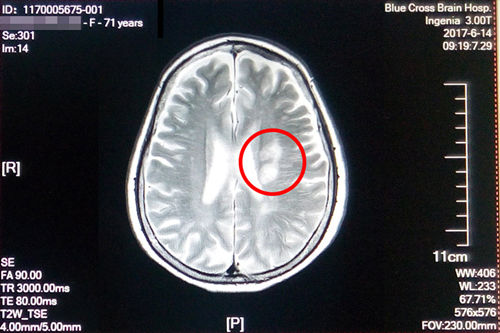

盛阿姨今年五月脑梗复发,在其他医院经过治疗后有所好转,在之后的康复治疗过程中病情又加重了,焦急的家属联系到了“蓝十字”。经过神经内科初步检查诊断,盛阿姨左侧侧脑室旁脑梗塞(急性期),脑干、双侧基底节区及额、顶叶多发腔隙性梗塞;大面积脑梗还造成了言语不清和偏瘫。入院时,右上肢肌力3级,左上肢肌力4级,双下肢肌力3级,因此无法行走,病情较重。

术前磁共振影像显示:患者多发性大面积脑梗

更为严重的是,入院后在DSA检查中还发现患者左侧大脑中动脉已经出现70%以上的狭窄,非常危险。李振并主任解释,脑血管狭窄是造成缺血性脑血管病的一个重要病因和危险因素,脑血管狭窄使得经过脑血管的血液减少,脑细胞就会缺血死亡。在临床上,脑血管狭窄程度在50%以下通过药物治疗,在50%-70%之间就要进行通过血管介入进行腔内血管成形术(球囊扩张支架置入术),而70%以上必须马上通过血管介入进行腔内血管成形术(球囊扩张支架置入术),否则一旦脑细胞因缺血大量死亡,患者会有性命之忧。